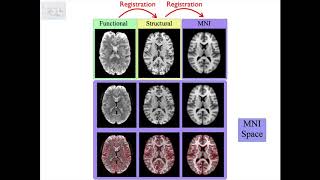

Registration

Registration: Image Registration and Distortion Correction

2. Registration: Image Spaces and Spatial Transformations

4. Registration: Single Stage and Multi-Stage Applications